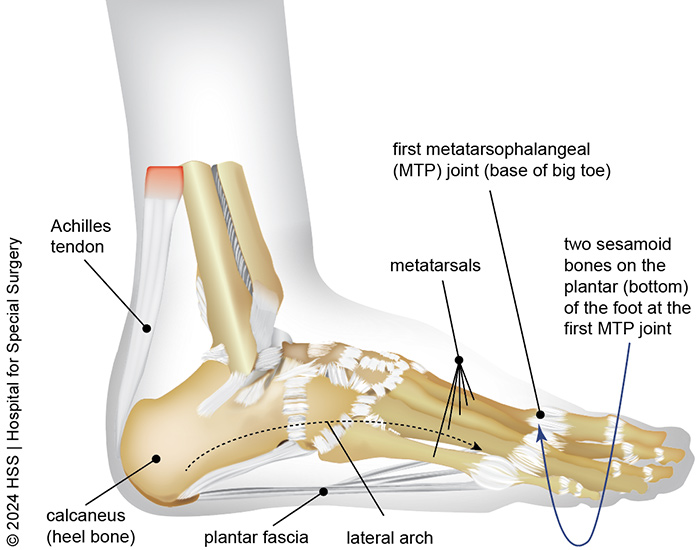

Foot Pain Conditions Causes Symptoms Treatments HSS

Foot Ankle Tendons Anatomy Function Injuries

Tendon from big 2024 toe to heel